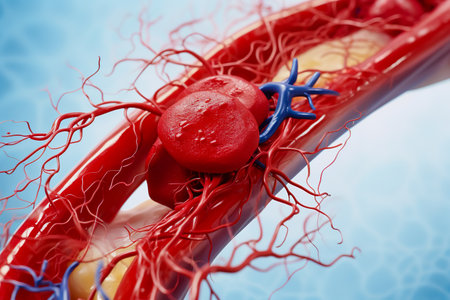

Aneurism of ascending aorta. Heart with aortic aneurism isolated on black background, 3D illustration